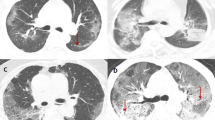

The clinical and CT characteristics of patients who progressed to severe COVID-19 (progressive group) and patients who did not (stable group) in the derivation cohort are presented in Table 2. Compared with those in the stable group, patients in the progressive group were significantly older (median age, 58 vs. 41 years old, P = 0.001) and more likely to have underlying hypertension (P = 0.004). But no significant difference was found in gender, exposure history, smoking history, and other co-morbidities including diabetes, chronic obstructive pulmonary disease (COPD), cardiovascular disease, cerebrovascular disease, and chronic hepatitis B infection between the two groups. The main clinical symptoms between the two groups were not statistically different, while slightly more patients manifested anorexia (P = 0.088), diarrhea (P = 0.065), and shortness of breath (P = 0.088) in the progressive group. There was no significant difference in percutaneous oxygen saturation on admission between the two groups (P = 0.110). Patients in the progressive group had lower baseline lymphocyte count and albumin, and higher NLR, aspartate aminotransferase, lactic dehydrogenase, and C-reactive protein (all P < 0.05). The major CT features of COVID-19 pneumonia patients were bilateral, peripheral or mixed distributed GGO, consolidation, and GGO with consolidation (Fig. 2a–f). Patients in the progressive group had more lobes and segments involved, with a higher proportion of crazy-paving sign and higher CT severity score (Supplementary Fig. 1a) compared with those in the stable group (all P < 0.05). However, no significant difference was found in hospital length of stay (P = 0.398) and duration of viral shedding after illness onset (P = 0.087) between the two groups.

a Subpleural patchy areas of GGO with crazy-paving sign in the right middle lobe. b Multiple patchy areas of consolidation in the right middle lobe, left upper lobe, and bilateral lower lobes and air bronchogram in the right middle lobe. c Multiple patchy areas of organizing pneumonia in the right middle and lower lobes on the sagittal image with CT severity score of 9 for the right lung. d Bilateral and peripheral multiple patchy areas of GGO with reticular and intralobular septal thickening. e Multiple mixed distributed pure GGO, GGO with consolidation, and interlobular septal thickening in bilateral lungs. f Bilateral multiple patchy and thin areas of GGO in the posterior parts of the lungs.